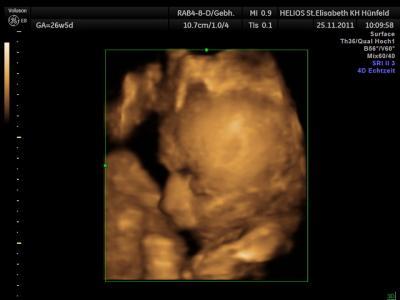

Hallo Mäuse :D waren heute wieder beim FA - unserem Sohnemann gehts Bestens - er ist Putzmunter und Quietschfidel - CTG war einwandfrei - Herztöne regelmäßig und kräftig - Blutdruck von der Mama war auch richtig gut und unser Schatz ist wiegt nun 1.400 Gramm :D Also alles in allem Prima und wir sind sehr GlÜCKLICH und sehr DANKBAR :D Und das Beste: Habe bis jetzt gesamt 5 Kilo zugenommen - also auch total im Rahmen :-) Haben dann wieder in vier Wochen den nächsten Termin - und dann noch zwei drei Termine und Schwupps können wir endlich knuddeln und unseren Sonnenschein in die Arme schließen :D Wünsch Euch noch einen wunderschönen Abend und ein tolles WE und weiterhin alles Liebe und Gute :D VLG. Annabelle, Oli und klein Eric im Bauchi

Bild zu zurück vom FA :D - Forum für Februar - Mamis